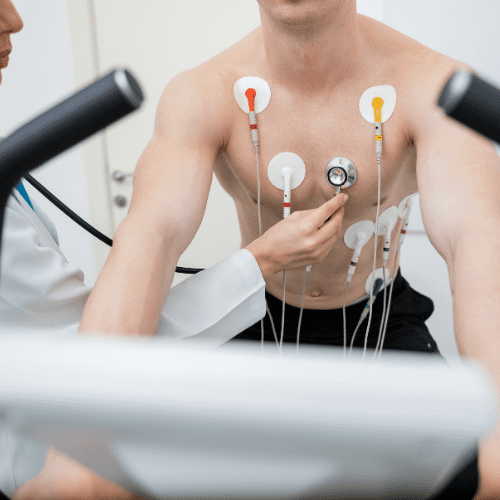

TMT

Heal and Health Hospitals provides a TMT (Treadmill Test) to assess heart function and detect cardiac issues under stress. Our cardiac experts use modern diagnostic equipment to evaluate heart health, ensuring early detection and effective treatment planning.